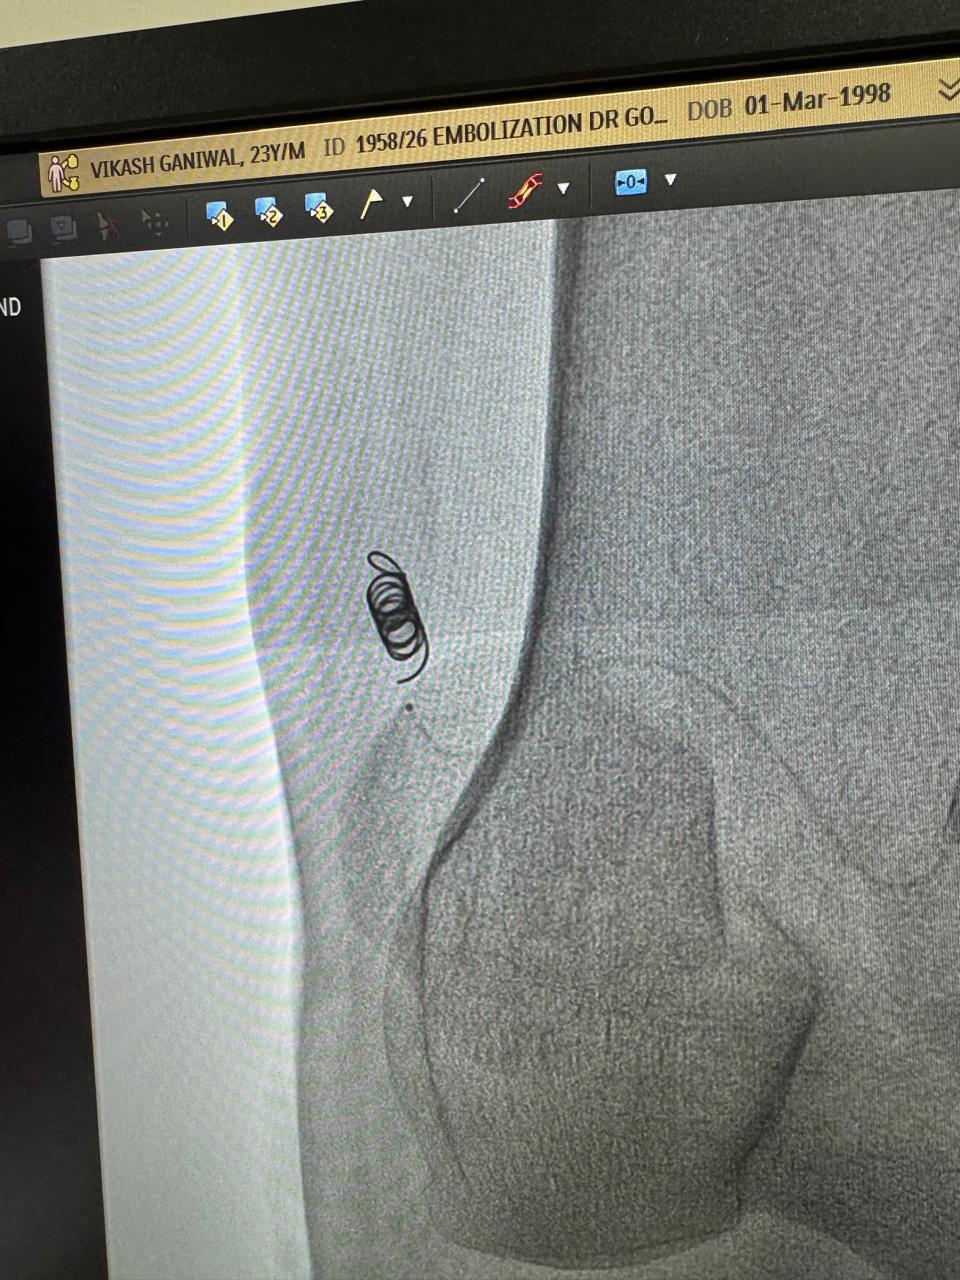

Vascular embolization of arteriovenous malformation